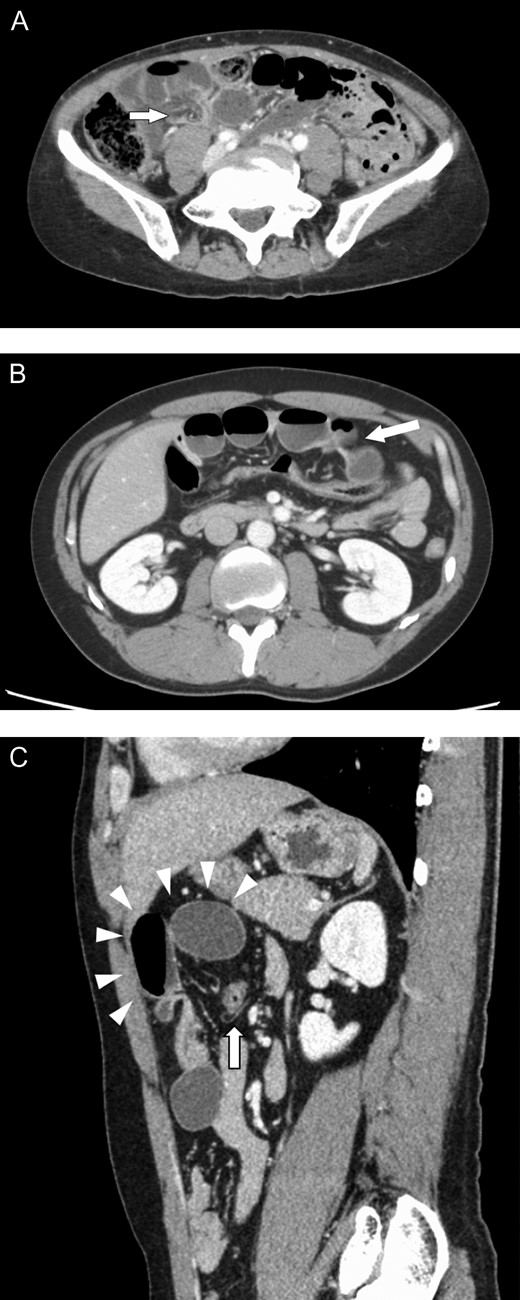

The first patient was a 58-year-old female who presented to our hospital with abdominal pain and vomiting; she had no history of abdominal surgery. Upon performing an examination, her abdomen was soft, with no guarding or rebound tenderness; however, central abdomen palpation revealed tenderness. A laboratory investigation revealed no abnormalities; however, enhanced abdominal computed tomography (CT) revealed intestinal obstruction of the right lower quadrant with the beak sign, indicating the transition zone of SBO (Fig. 1A). Therefore, the patient was diagnosed with strangulation ileus due to the internal hernia. Emergency laparoscopic surgery revealed an incarcerated loop of the small bowel through a greater omental defect (Fig. 2A). The incarcerated small bowel was released; because the ileal segment was viable, bowel resection was deemed unnecessary. The patient was uneventfully discharged on postoperative Day 8.

Enhanced abdominal computed tomography findings. (A) The beak sign (arrow) is indicated in the lower right quadrant. (B) Small bowel loops with caliber change (arrow) are indicated in the upper abdomen. (C) A peripheral herniated loop (arrowheads) within the peritoneal cavity. The transverse colon is indicated by an arrow.

The second patient was a 36-year-old male who presented to our hospital with abdominal pain and had no history of abdominal surgery. His physical examination revealed upper abdominal tenderness. Laboratory investigations revealed no abnormalities except for an abnormal white cell count (11 000 mm3). Enhanced abdominal CT revealed dilated, fluid-filled loops of the small bowel, with caliber change in the upper abdomen (Fig. 1B and C). He was suspected of having transomental hernia, and emergency laparoscopy was performed. During surgery, an ileal segment measuring ~15 cm in length was observed to be herniating through a greater omental defect (Fig. 2B). The small bowel was released by dividing the omentum; there was no evidence of ischemic changes in the incarcerated loop of the small bowel. The postoperative course was uneventful; the patient was discharged on postoperative Day 4.

Internal hernia is a rare cause of SBO, with transomental hernia, which accounts for only 1–4% of all internal hernias, being even rarer [1, 2]. Spontaneous transomental hernia typically occurs because of senile atrophy of the greater omentum in patients with no history of abdominal surgery, trauma or inflammatory disease [3]. Symptoms can range from mild, chronic and intermittent abdominal pain to acute severe abdominal pain caused by strangulated SBO associated with nausea and vomiting. Moreover, patients with transomental hernia more frequently present with gangrenous bowel than those with other internal hernia types [4], making rapid diagnosis and treatment for avoiding bowel resection important. Although abdominal CT helps diagnose transomental hernia based on its characteristic features, the features are not universal, which makes diagnosing these hernias difficult [5]. This was exemplified in our patients, wherein the second showed classic peripheral herniated loops within the peritoneal cavity, whereas the first showed no classic features.